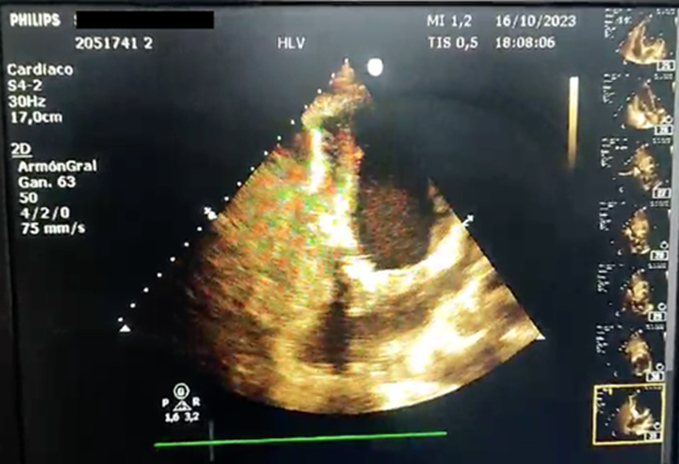

El tratamiento consistió en reparación quirúrgica del pseudoaneurisma usando parche de Dacron para tapizar el sitio de ruptura miocárdica cubriendo parte del septum y segmento posterior, se realiza ecocardiograma transquirúrgico.

Ilustración 6 Evidencia mejoría inmediata de la FEVI 58%.

Fuente: Hospital de Especialidades Guayaquil “Doctor Abel Gilbert Pontón”.

Autor: Dra. María Sánchez Sánchez.